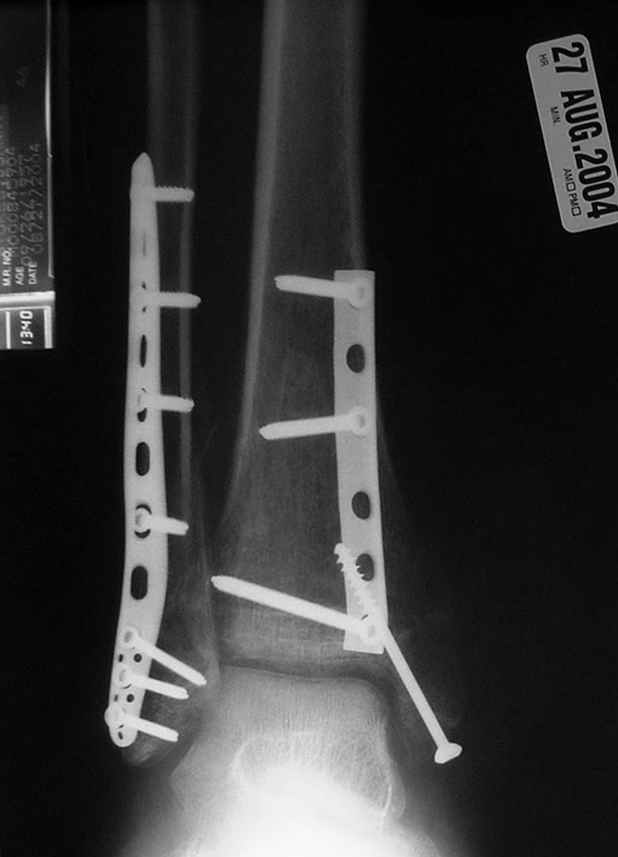

Второй случай сделан из одного разреза

Дж

ЕЧ LISS plate, mininvasive approach - luxurous !

На прямой проекции послеоперационного Рг макроскопически все выглядит очень анатомично, при микроскопическом ( :-)) ) рассмотрении можно все-таки заметить вальгизацию тарана, суставная щель в латеральном отделе сустава несколько уже , чем в медиальном при отсутствии латерального смещения тарана. У меня был аналогичный случай (без LISS , без мини доступа) с вальгусным наклоном тарана при восстановленном ankle mortise при последовательном наблюдении с интервалами в 6-8 недель в послеоперационном периоде отмечалось прогрессирующее сужение суставной щели в латеральном отделе сустава, закончившееся посттравматическим ОА, к счастью боли умеренные, купируемые аналгетиками или своими эндорфинами:-))(активная пациентка, у которой нет времени на болезни....) Какова жизненная ситуация в приведенном вами случае? И последнее, что я хотел бы прояснить для себя - фиксация внутренней лодыжки: я обычно комбинирую фиксацию компрессирующим винтом со спицей - по идее ротационная стабильность должна быть лучше, чем один винт, каковы ваши наблюдения в этом плане?